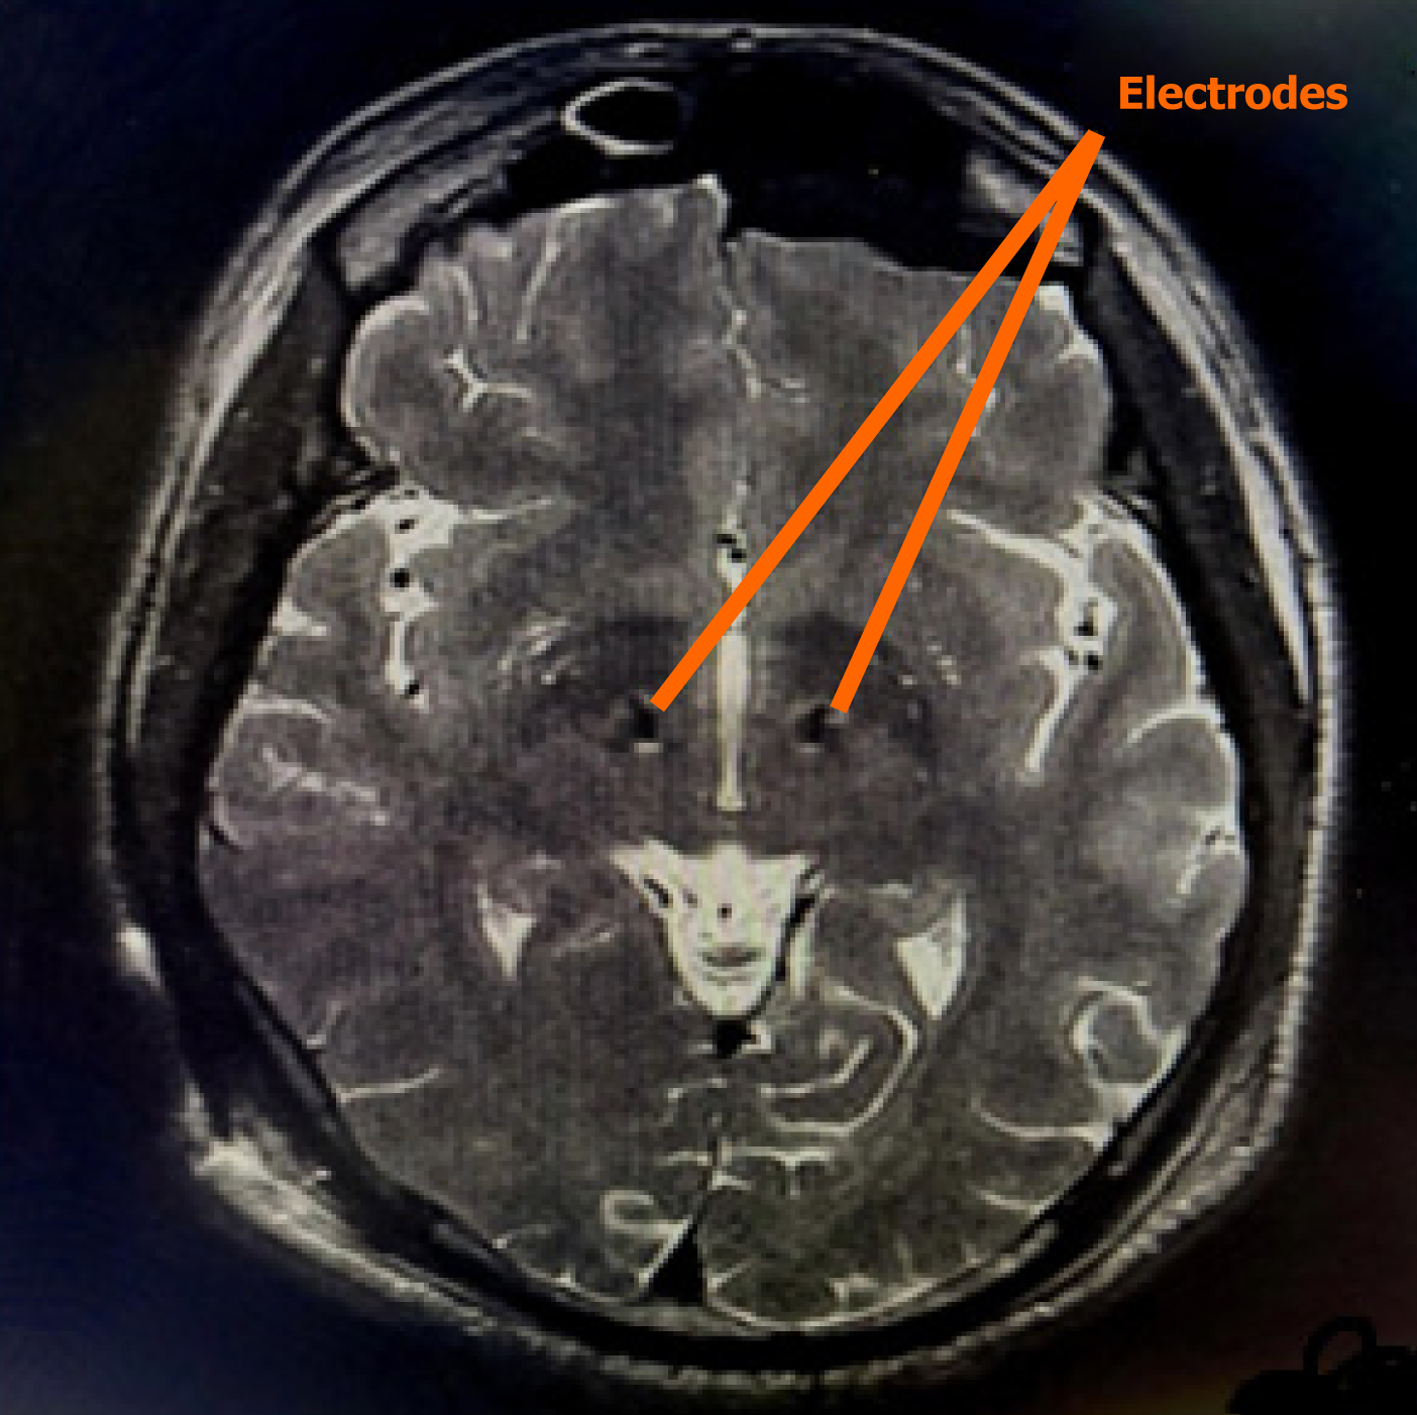

Figure 2 Post-op axial T2 weighted magnetic resonance imaging showing bilateral deep brain stimulation electrodes placed in sub thalamic nucleus (orange arrow).